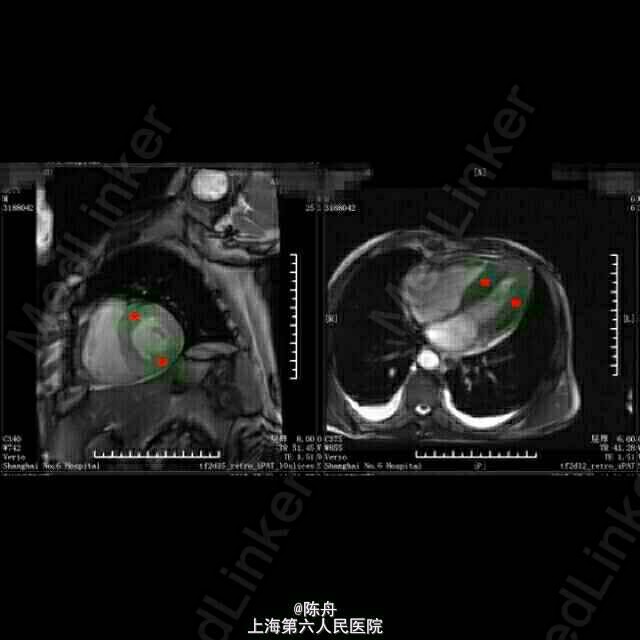

查体:BP 90/60 mmHg,神志清醒,气平,无贫血貌,颈静脉怒张,舌头正常,双肺听诊呼吸音清,双肺未及干啰音。心浊音界大致正常,心率74次/分,律齐,P2=A2,心音减低,各瓣膜区未闻及病理性杂音。腹壁柔软,无腹部压痛,肝脾未触及。双下肢轻度水肿。无关节肌肉疼痛。 辅助检查: 血常规:白细胞 6.7 *10^9/L ,血红蛋白 120 g/L ↓,血小板 218 X10^9/L ,中性细胞百分比 46.5 % 。血沉: 34 mm/h 。C反应蛋白 8.53 mg/L ↑。 肝肾功能:总蛋白 44 g/L ↓,白蛋白 29 g/L ↓,谷丙转氨酶 43 U/L ,谷草转氨酶 72 U/L ↑,总胆红素 9.0 μmol/L ,直接胆红素 5.5 μmol/L ,总胆汁酸 3.1 μmol/L ,前白蛋白 170 mg/L ↓,总胆固醇 2.40 mmol/L ↓,甘油三脂 1.38 mmol/L ,高密度脂蛋白 0.48 mmol/L ↓,低密度脂蛋白 1.48 mmol/L ↓,肌酸激酶 194 U/L ↑,CK-MB 16.0 U/L ,乳酸脱氢酶 334 U/L ↑,α羟丁酸脱氢酶 282 U/L ↑,血清钾(干式) 3.3 mmol/L ↓,血清钠(干式) 134 mmol/L ↓,血清氯(干式) 91 mmol/L ↓,钙(干式) 1.94 mmol/L ↓,尿素(干式) 19.0 mmol/L ↑,肌酐(干式) 87 μmol/L。 血气:PH 7.40 ,二氧化碳分压 39.7 mmHg ,氧分压 79.8 mmHg 生化报告:清蛋白 49.2 % ↓,α1球蛋白 8.6 % ↑,α2球蛋白 18.6 % ↑,β1球蛋白 6.3 % ,β2球蛋白 2.9 % ↓,γ球蛋白 14.4 % 。 免疫:血清KAPPA轻链 2.80 g/L ,血清LAMBDA轻链 0.26 g/L ↓,κ/λ比值 10.81 ↑。 免疫:尿KAPPA轻链 1260.00 mg/L ↑,尿LAMBDA轻链 4.62 mg/L ↑。 其它免疫指标全阴性. 甲状腺功能:游离T3 2.81 pmol/L ↓,游离T4 19.94 pmol/L ,促甲状腺激素 2.71 mIU/l 。 生化:肌钙蛋白-I 0.305 ↑,CKMB 9.6 ug/L ↑,B型钠尿肽(BNP) 1260.00 ng/L ↑。B型钠尿肽前体(proBNP) >35000 ng/L ↑。 心脏超声: 1.左心房稍扩大2.左室壁增厚3.未见节段性室壁运动异常。EF:60% 24H动态心电图:1.窦性心律2.房性早搏(时呈成对,代偿后见室性逸搏)3.房性心动过速(短阵)。终止后呈窦性,交界性逸搏,恢复时间<2秒。4.室性早搏(多源性,时呈成对,二联律)5.ST段下移,T波倒置(持续性:第一,三通道导联,呈水平型)6.未见传导异常。 心脏 MRI:1.双心室壁增厚,收缩功能保留,心肌淀粉样变可能。2.微量心包积液,少量双侧胸腔积液。 胸部CT:1.慢性支气管炎,两肺多发微小结节,考虑炎性肉芽肿可能。2.心脏增大,两侧胸腔积液,伴下肺膨胀不全。 电子胃镜:糜烂性浅表性胃炎。病理:阴性。

随访:1周后失联 淀粉样变(Amyloidosis)是指不溶性蛋白质沉积在组织或器官并导致其功能异常的一组疾病。1853 年病理学家 Virchow 发现了一种嗜酸性均匀一致的物质沉积在组织或器官中,因这种物质对碘的颜色反应与淀粉相似而命名为“淀粉样物质”,并将由于此类物质沉积所导致的一组疾病称为淀粉样变。近四十年研究证实此类物质是蛋白质,而非淀粉样碳水化合物,但至今仍沿用“淀粉样变”这一术语。 淀粉样变可以影响多系统器官,尤其以肾脏、心脏、肝脏、神经、胃肠道等病变严重,也可以累及肌肉和骨关节。目前淀粉样变的分类较为混乱,尚没有统一、完善的分类。根据临床特点,淀粉样变可以分为系统性或局灶性,获得性或遗传性。获得性系统性淀粉样变包括:AL(原发性)、AA(继发性、反应性)和 Aβ2-M(透析相关性)。 淀粉样变的病因不同,病理形态学改变却拥有共同的特征。现已证实,淀粉样变沉积物质具有共同的核心结构,即与淀粉样物质长轴垂直的反平行β折叠层片样结构。这种空间组织形式决定了它与刚果红染色的高度亲和力。偏光镜下,被刚果红染色的淀粉样沉积物质出现苹果绿色双折射光,这是淀粉样变病理学诊断要点。 心脏受累可导致心脏肥大、心律失常和心力衰竭,是 AL 淀粉样变患者最常见的死因。 治疗的主要原则是减少/干预前体蛋白合成,稳定前体蛋白的自身结构,破坏淀粉样蛋白的稳定性,以及积极对症处理。 该患者为67岁男性,发病以右心功能不全为主要表现:颈静脉怒张,胃肠淤血,双下肢水肿,实验室检查:肌钙蛋白-I 0.305 ↑,CKMB 9.6 ug/L ↑,B型钠尿肽(BNP) 1260.00 ng/L↑,B型钠尿肽前体(proBNP) >35000 ng/L ↑,血清κ/λ比值升高,尿中有大量KAPPA轻链,肝肾功能及其它免疫指标大致正常;心脏超声示左心房稍扩大,左室壁增厚,EF:60%。心脏MRI示双心室壁增厚,收缩功能保留,心室肌细胞间可见颗粒样物质沉积。结合患者临床表现及实验室检查,及肾内科、内分泌、血液科会诊意见,考虑心脏淀粉样变。若条件容许,可进一步行右心导管术及心内膜活检以明确诊断。该患者入院第二天即出现血压下降,多巴胺维持;入院第四天出现心率下降,心电图由入院前窦性心律,肢体导联低电压,T波改变(V3~V6倒置),变为:交界性逸搏节律,逸搏-夺获二联律,给予异丙肾上腺素维持心率。积极对症处理无效,患者及家属放弃继续治疗。 【经典病例,仅供内部学习,请勿刊发】 【感谢各位同道点评和指教】